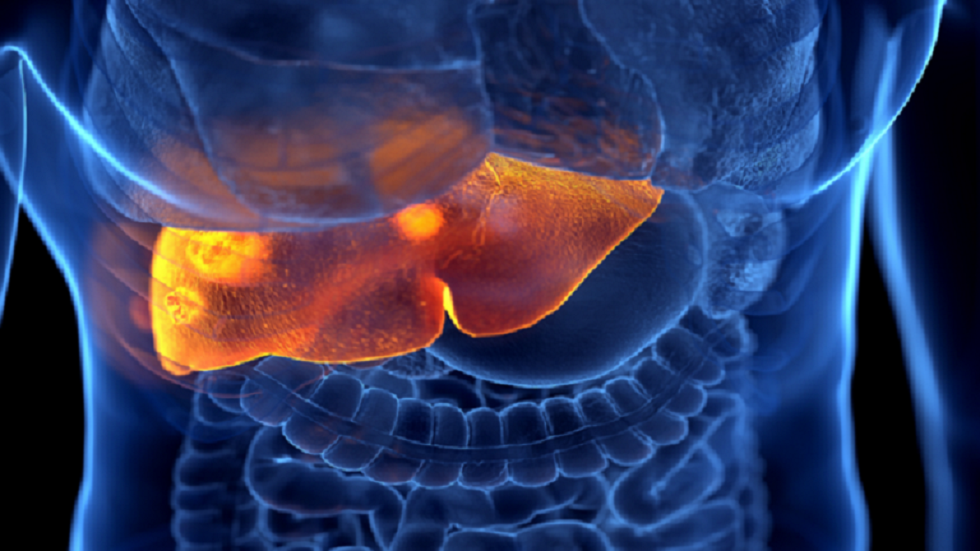

وأضافت “أثناء الفحوصات، تم اكتشاف فشل كبدي ووذمة دماغية، وعلى الرغم من جهود الأطباء، توفي الطفل”.

وتم الإبلاغ عن 11 حالة أخرى في اليونان ظهرت عليها أعراض التهاب الكبد الحاد مجهول المنشأ لدى الأطفال، أغلبها لم تتطلب علاجات خاصة، ولم تكن مصحوبة بمضاعفات.

ووفقا لتقارير منظمة الصحة العالمية، فقد تم تسجيل 920 حالة لالتهاب الكبد مجهول المنشأ في 33 دولة في جميع أنحاء العالم، وتطلبت 45 حالة (5 في المئة) زراعة كبد، وانتهت 18 حالة (2 في المئة) بالوفاة، مؤكدة أنه “في الأسابيع الأخيرة شهد العالم تراجعا مطردا في حالات الإصابة بالمرض”.